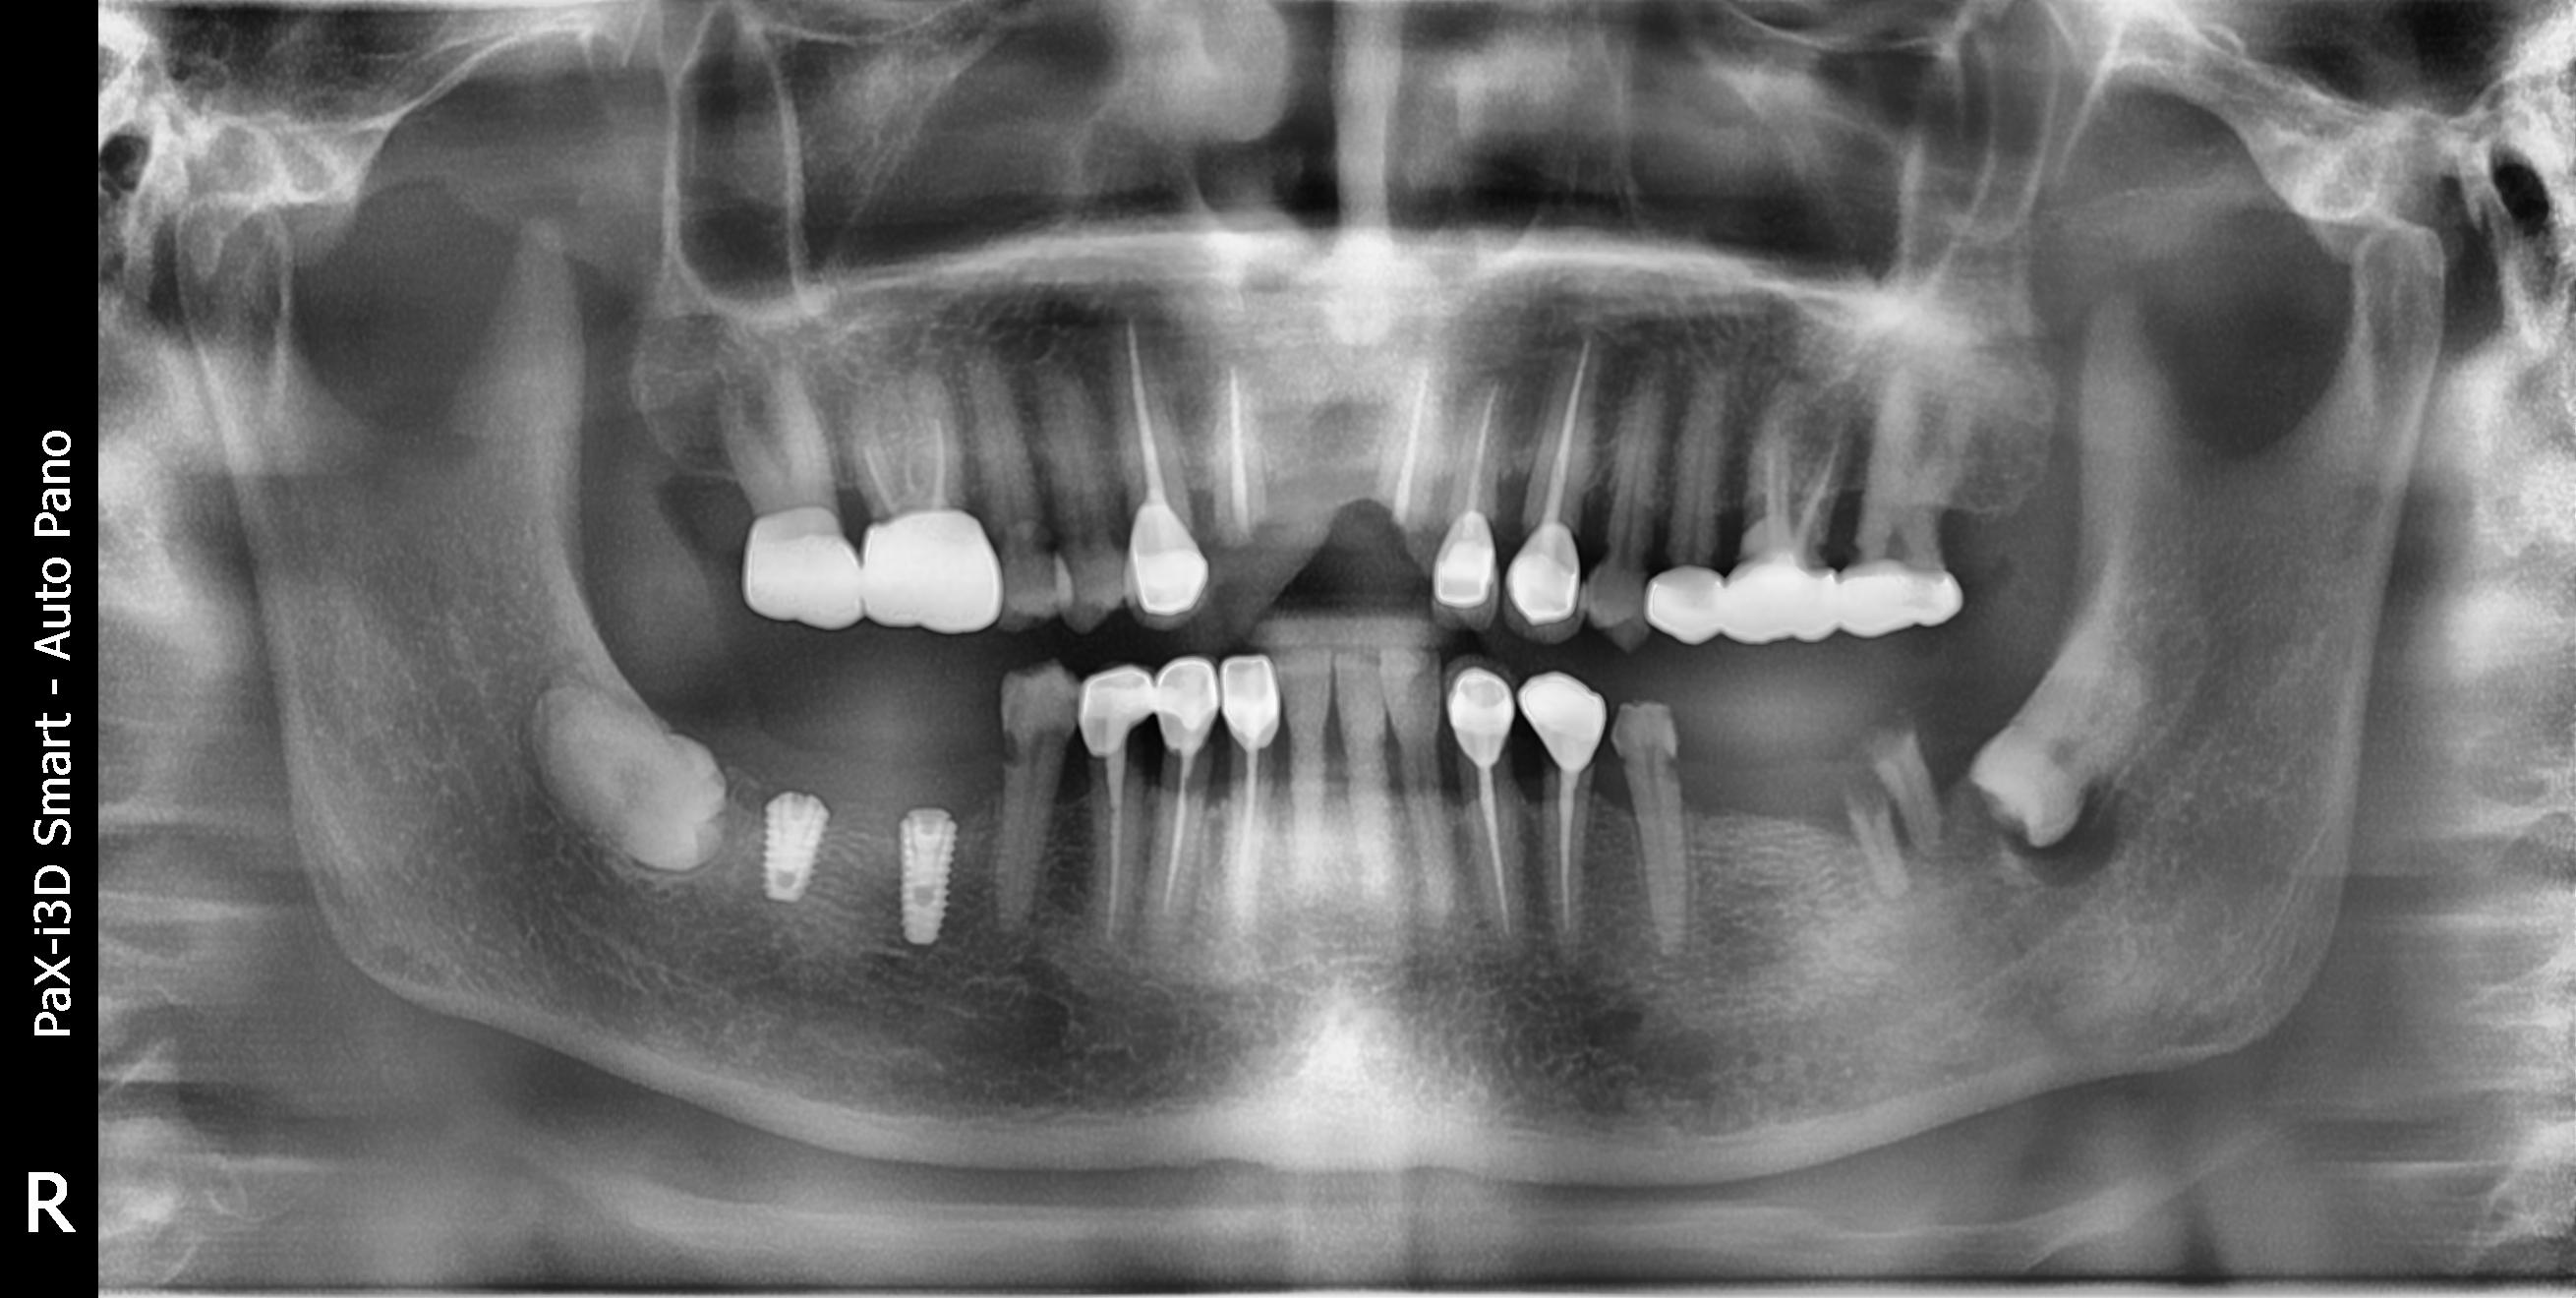

사랑니는 사랑을 하게 되면 그 존재감을 들어낸다는 속설이 있습니다. 저의 경우 6개월에 1번씩 검진을 받고 있는데 어느 날 담당 주치의 선생님께서 이제 사랑니를 뽑을 때가 되었다고 하셔서 당일 아무런 준비도 없이 그냥 사랑니와 매복 사랑니를 하나씩 뽑았습니다. 지금 생각해 보면 남은 1개마저 뽑을껄 무서움에 2개만 뽑은 게 후회가 됩니다. 2개를 뽑는다고 해서 고통이 2배인 것은 아니었으니 3개를 뽑아도 고통은 똑같았을 것 같습니다. 턱 주변이 붓고 얼굴이 이상하게 붓고 열감과 가끔 오는 통증 때문에 휴식도 마음 편하게 취하지 못했습니다.

치과 치료를 하면 알 수 있는 것이 치아는 함부로 뽑지 않습니다. 정말 최대한 살려보고 그래도 안 되면 뽑아서 임플란트 등으로 빈자리를 채웁니다. 사랑니는 다른 치아들과 달리 발치를 해야 할 때도 있습니다. 잘 자란 사랑니는 특별한 문제를 일으키지 않아 뽑지 않아도 됩니다. 하지만 대부분의 사랑니는 말썽을 부립니다. 출혈, 염증, 통증 및 악취, 충치 들 여러 가지 문제를 일으킬 확률이 높기 때문에 뽑아야 합니다.